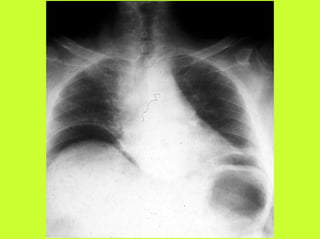

3) RADIO (PNO)

RADIOGRAPHIES

ABDOMEN SP -scanner

PNEUMOPERITOINE SUR SUJET DEBOUT

" Croissant gazeux sous diaphragmatique

" Disparition du niveau hydroaérique gastrique

PNEUMOPERITOINE SUR SUJET COUCHE

" Visibilité du ligament triangulaire du foie

" Visibilité anormale des parois intestinales

" Image aérique pré-hépatique

"Pneumatisation de MORRISSON

(cul de sac inter-hépato-rénal)